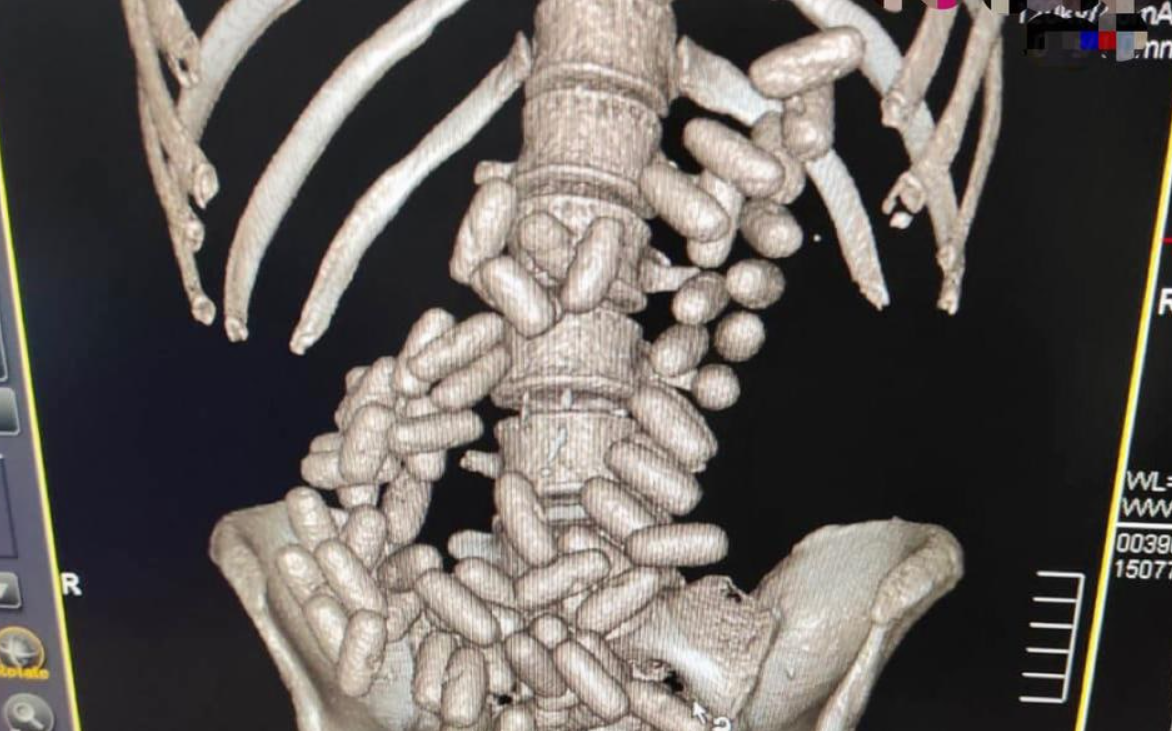

Citing "serious doubts about his law-abidingness", customs officials took the passenger for an inspection, which extended to an abdominal cavity scan.

Read alsoSBU prevents illegal shipment of military goods to RussiaPerformed by a certified medic, a CT check revealed dozens of capsules inside the culprit's body.

Following a medical extraction routine, which lasted for 19 hours, customs operatives saw a total of 91 capsules filled by cocaine, with a net weight of 1,070.29 grams.